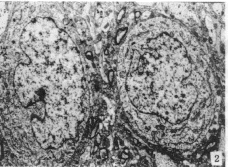

1.1 丙烯腈组 毛细血管:内皮细胞畸形,核、质比例大,胞体瘦小扁平,胞浆菲薄。有的内皮细胞末端向管腔面突出外翘,与管腔壁成90°,但内皮细胞与基膜及其周围神经毡之间结构紧密(图1)。神经细胞:胞体变圆,核畸形多见,有的为深裂,有的核膜内陷,胞质随同陷入核内,核膜包绕胞质形成岛状区域。核周质内可见大量游离核糖体但尼氏体少,部分线粒体脊断裂、消失呈空泡化(图2)。

图1 丙烯腈组毛细血管:内皮细胞畸形,末端向管腔面突出,但与基膜及神经毡之间结构紧密 ×4 000 图2 丙烯腈组神经细胞:胞体变圆,核畸形多见 × 4 000 图3 丙烯腈加酒精组毛细血管:内皮细胞萎缩,染色质高度浓缩呈凋亡状态 ×4 000 图4 丙烯腈加酒精组毛细血管:内皮细胞基膜与周围神经毡之间形成很大的空隙 ×4 000 图5 丙烯腈加酒精组神经细胞:染色质浓缩并挤向一边核膜 ×5 000 图6 丙烯腈加酒精组神经细胞:凋亡小体被附近的神经细胞吞噬 ×5 000